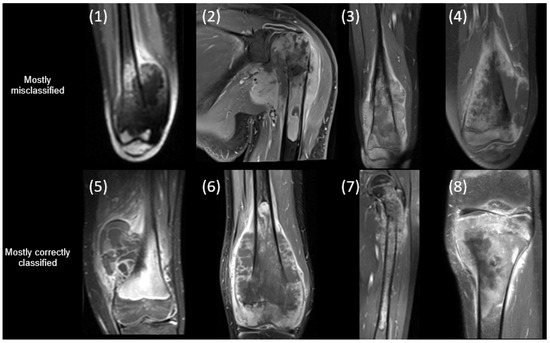

| Patient | Gender | Age (y) | Skip Lesion | Meta-Stasis | OS Type | Progressive Disease | % Necrosis | Relapse off Therapy | Mortality |

|---|---|---|---|---|---|---|---|---|---|

| 1 | Female | 14.0 | No | Yes | Osteobl. | No | 100 | Yes | Yes |

| 2 | Male | 16.3 | No | Yes | Osteobl. | No | 99 | No | No |

| 3 | Female | 14.9 | Yes | Yes | Osteobl. | Yes | >99 | Yes | Yes |

| 4 | Male | 10.9 | No | Yes | Chondrobl. | No | >99 | No | No |

| 5 | Female | 9.8 | No | No | Osteobl. and telangiectatic | No | 100 | No | No |

| 6 | Male | 12.3 | Yes | Yes | Osteobl. and chondrob. | Yes | 95 | Yes | Yes |

| 7 | Male | 9.0 | No | No | Osteobl. | No | 87 | No | No |

| 8 | Male | 14.2 | No | No | Osteobl. | Yes | 40 | No | yes |